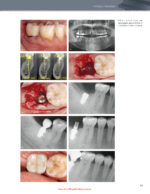

The Immediacy Concept: Treatment Planning from Analog to Digital 2022

کتاب افست “The Immediacy Concept: Treatment Planning from Analog to Digital 2022”